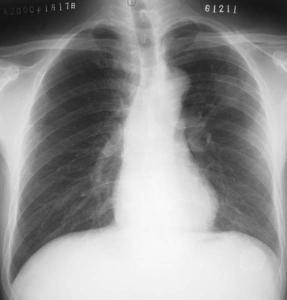

厌氧菌肺部感染是由厌氧菌引起的气管、支气管、肺实质、胸膜腔的炎症,厌氧菌种类繁多,致病力不尽相同,是引起肺部感染的常见病原菌之一。